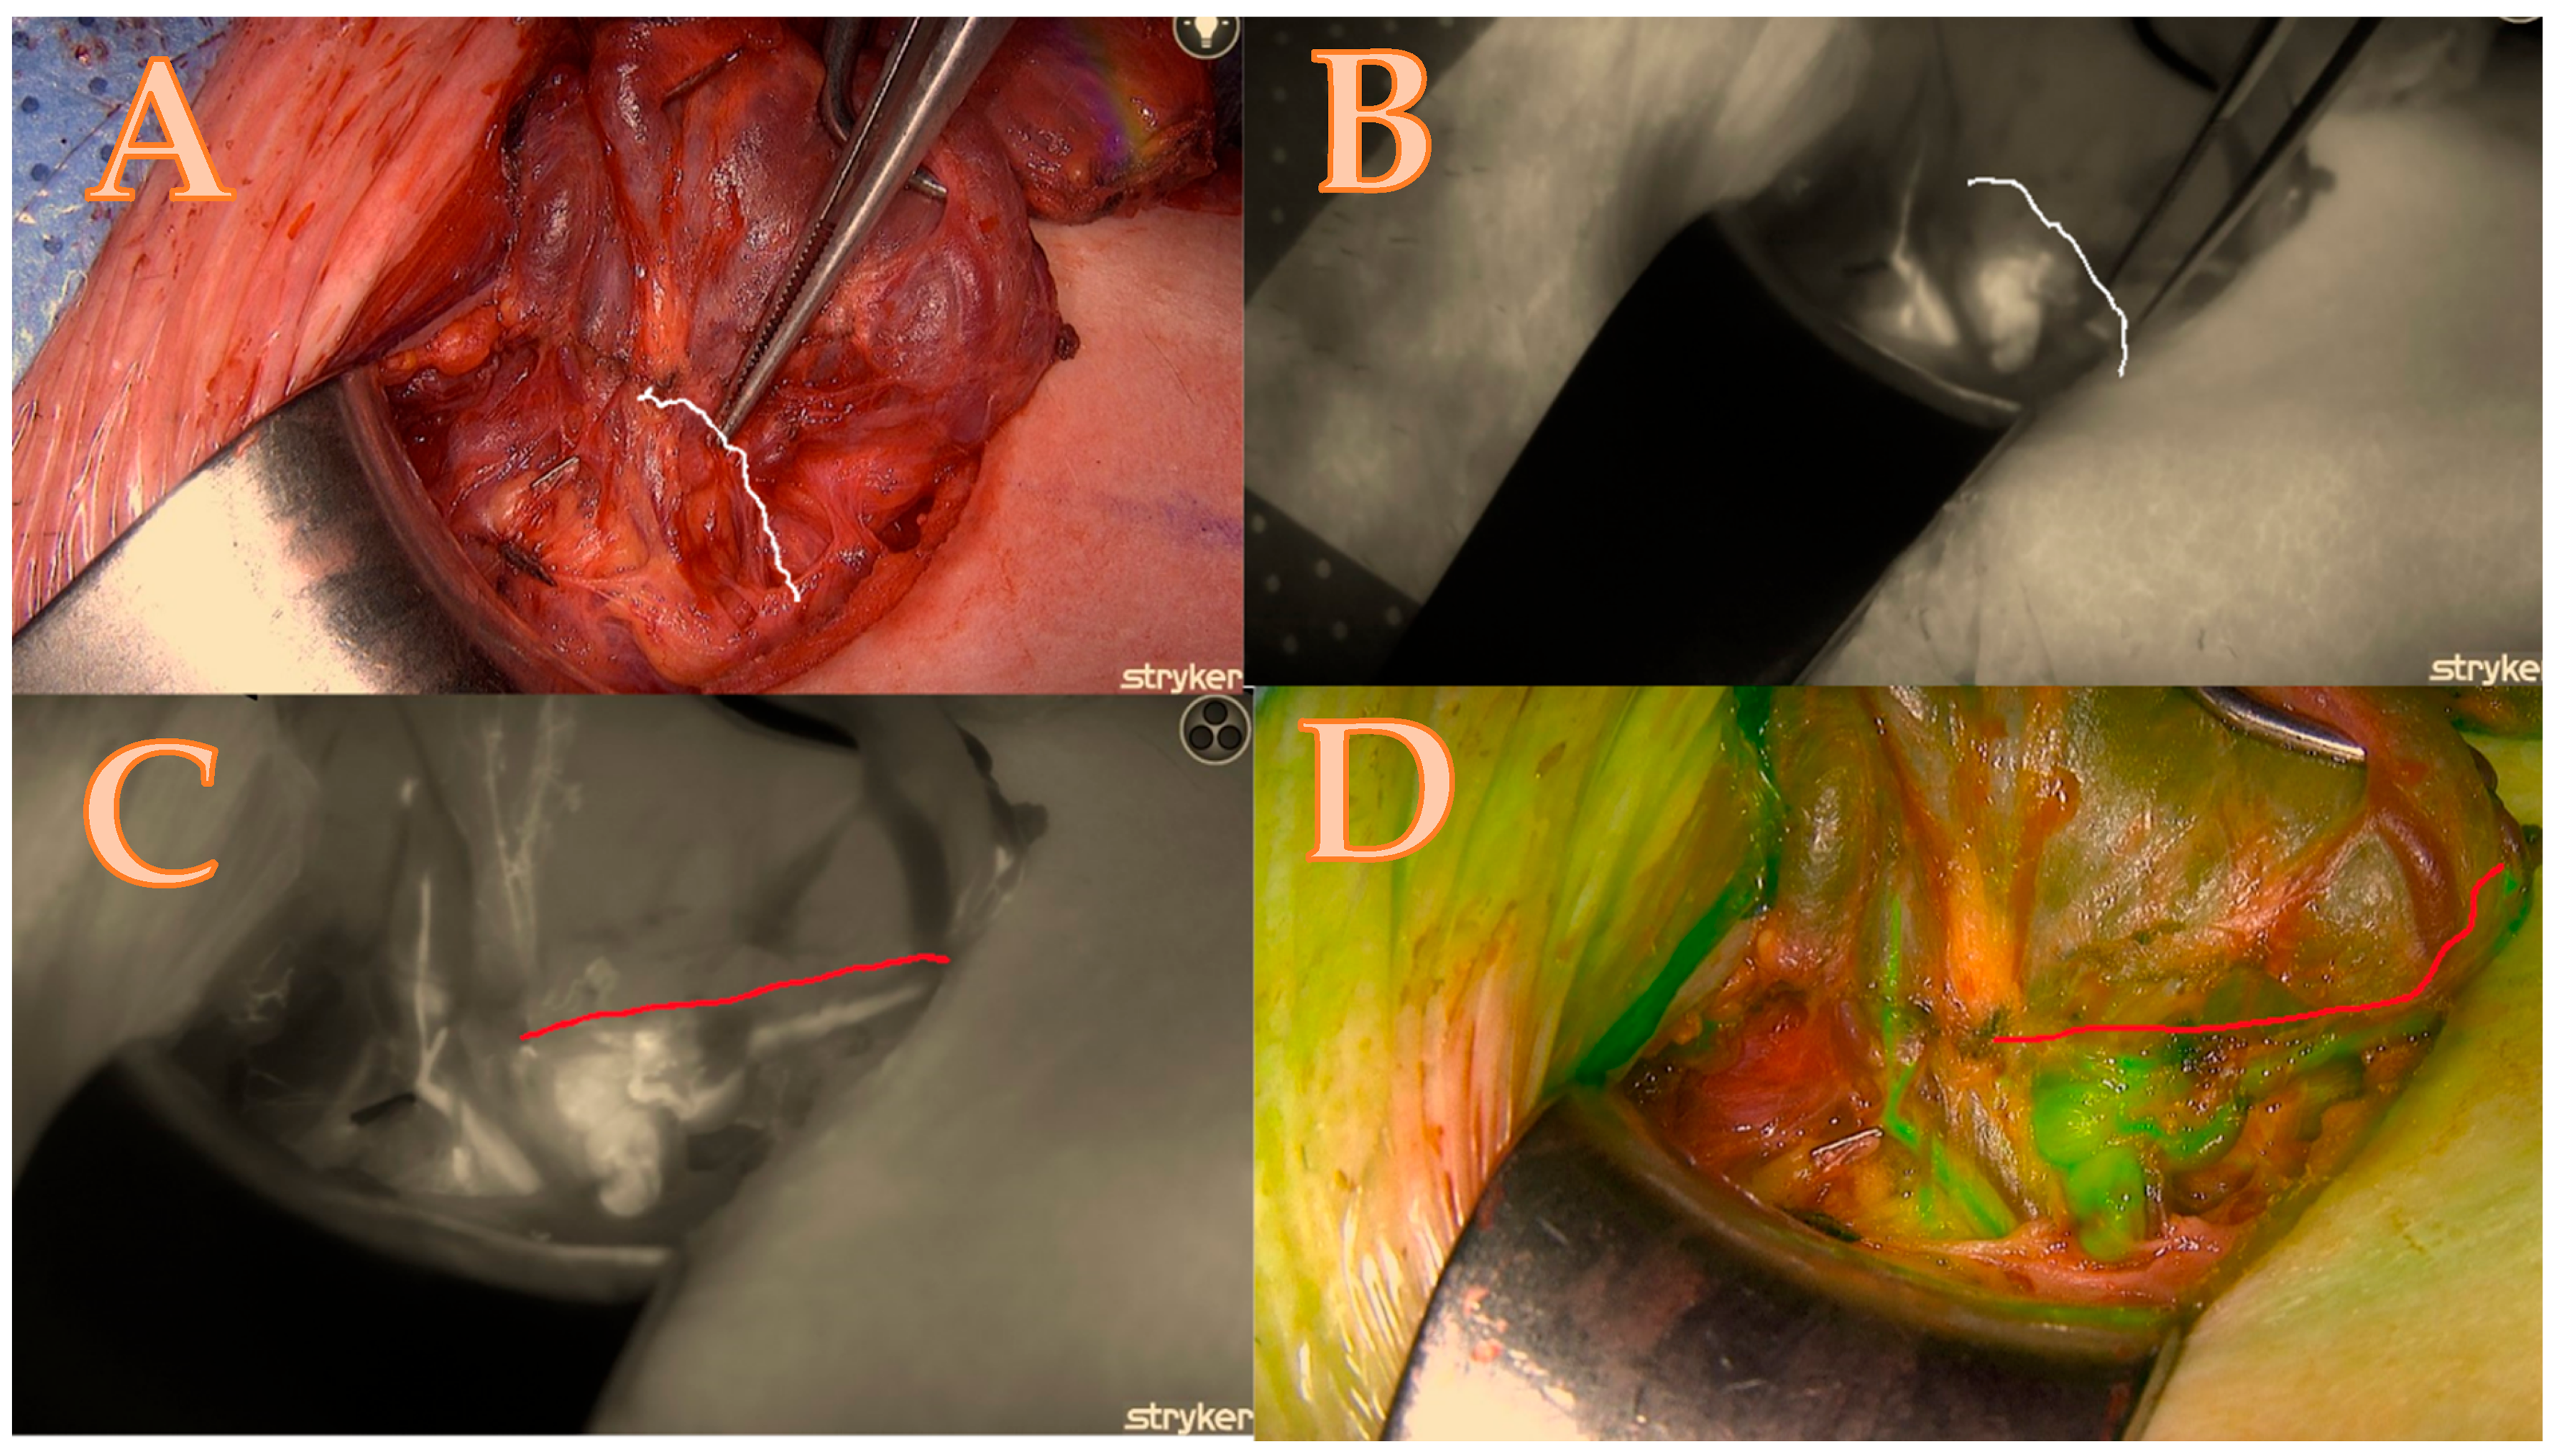

- The score ratio is calculated by dividing the total score by the maximum possible score and converting it into a percentage. In this case, 11/14 = 78.5%. This methodology allows for a comprehensive and standardized assessment of parathyroid gland viability, combining clinical assessment with advanced fluorescence imaging (see Table 1 and Figure 1, Figure 2, Figure 3 and Figure 4).